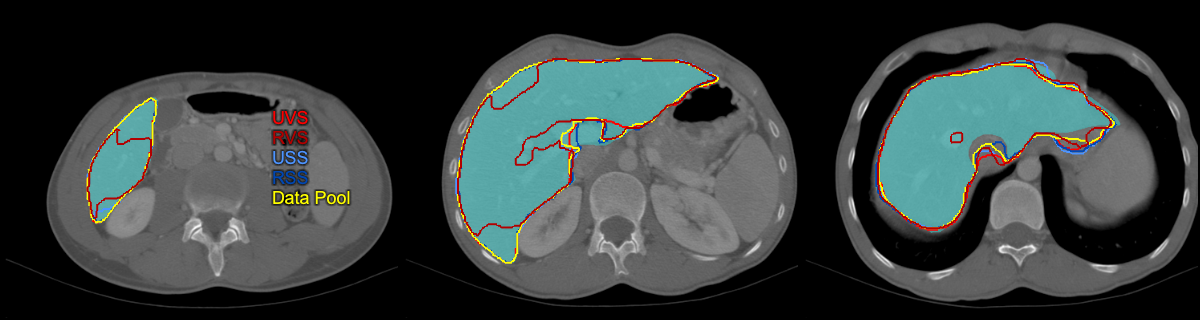

Refer to caption

(a) Polycystic liver case where the USS strategy resulted in the best segmentation: UVS 0.83 Dice, 25.2% RVE, 8.0 mm MSD, 64 mm HD; RVS 0.53, 63.2%, 18.0 mm, 64 mm; USS 0.94, 5.2%, 3.2 mm, 59 mm; RSS 0.84, 21.7%, 8.7 mm, 65 mm; Data Pool 0.85, 24%, 8.3 mm, 64 mm.

(b) Case where UVS outperformed all models: UVS 0.96 Dice, 0.4% RVE, 1.1 mm MSD, 17 mm HD; RVS 0.96, 3.1%, 1.4 mm, 21 mm; USS 0.94, 5.6%, 1.5 mm, 24 mm; RSS 0.95, 2.5%, 1.4 mm, 22 mm; Data Pool 0.93, 9.1%, 2.1 mm, 32 mm.

(c) Case where both random strategies resulted in overestimation in the caudal liver region: UVS 0.91 Dice, 6.1% RVE, 2.4 mm MSD, 23 mm HD; RVS 0.93, 3.4%, 2.1 mm, 25 mm; USS 0.95, 1.0%, 1.5 mm, 17 mm; RSS 0.77, 41.0%, 23.3 mm, 141 mm; Data Pool 0.94, 0.2%, 1.7 mm, 21 mm.

(d) Case for which all strategies except RVS achieved very good segmentation performance: UVS 0.97 Dice, 0.1% RVE, 0.9 mm MSD, 18 mm HD; RVS 0.91, 11.8%, 2.9 mm, 36 mm; USS 0.96, 1.8%, 1.0 mm, 20 mm; RSS 0.97, 1.6%, 0.9 mm, 20 mm; Data Pool 0.97, 0.0%, 0.8 mm, 20 mm.

Figure 3: Representative examples presenting segmentation output of the converged models and the model trained on the whole data pool.

In our work, we proposed the uncertainty slice sampling (USS) strategy in the context of pool-based active learning. Our strategy selects 2D image slices from a pool of 3D volumes using aggregated voxel-wise predictive entropy as the uncertainty measure. We evaluated the proposed strategy on a CT liver segmentation task and compared it with random slice sampling (RSS), uncertainty volume sampling (UVS), and random volume sampling (RVS) strategies. The model trained using the USS data (4% of available data) achieved significantly better results than the remaining strategies. Although after five active learning iterations the USS model was inferior in performance on average to the model trained on all available data, it provided more robust segmentation as measured by 5th DICE and 95th MSD metrics. We hypothesize that this can be attributed to differences in the training set composition. The training set resulting from the USS contains a bigger proportion of difficult/rare cases compared to the whole data-pool training set, which effectively causes that the model sees them more frequently during the training process. Fig. 3 shows exemplary outputs from the investigated models including two hard cases from the test set: a polycystic (Fig. 3(a)) and a resected (Fig. 3(b)) liver. We think that the robustness of the whole data pool model could be increased by employing a hard example mining during training to dynamically adjust the sampling rate of difficult examples[26, 27]. Selecting only uncertain cases in the course of active learning can overload the model with difficult examples causing a performance drop. This can be observed for the USS strategy after the first iteration (see Fig. 1, where the model performs substantially worse than its random counterpart (RSS).